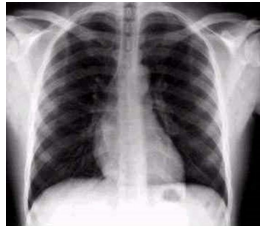

How does Asthma look on CXR?

Flattened diaphragm on chest X-Ray (CXR)